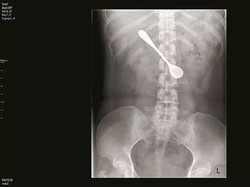

Mengeluh Sakit Perut, Ternyata Ada Beragam Perkakas Ditemukan di Lambung

Seorang pria di India datang dengan keluhan sakit perut yang tak tertahankan. Hasil pemeriksaan menunjukkan ada beragam perkakas bersarang di dalam perutnya.